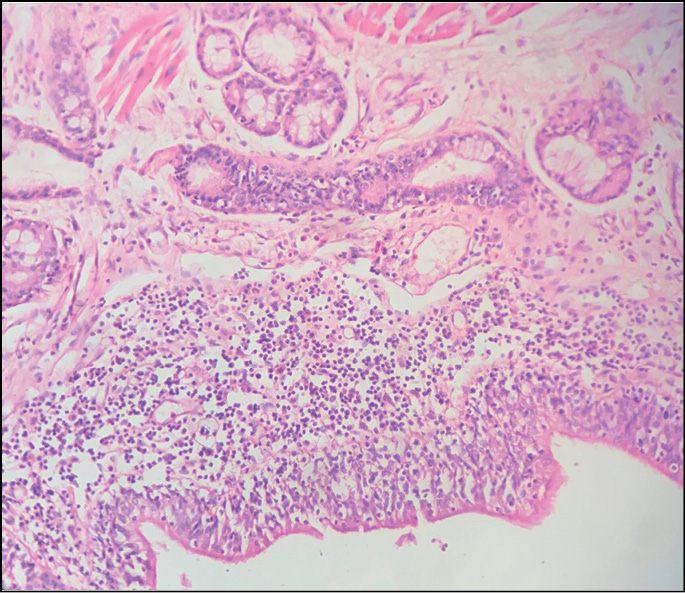

- очаги острой альвеолярной эмфиземы, дистелек-тазов, серозного отёка, интерстициального воспаления; мелкоочаговый альвеолит; нарушение гемодинамики в системе микроциркуляторного русла; в просветах сосудов эозинофилия разной степени выраженности (рис. 2); стенки бронхов с небольшой полиморфноклеточной инфильтрацией, наличием эозинофильных лейкоцитов (рис. 3); спазм бронхов и бронхиол (рис. 4), в просветах части бронхиол ― гомогенные бурые массы, клетки десквамированного эпителия (рис. 5); отёк висцеральной плевры;

Рис. 5. Наличие в просвете бронхиол гомогенных бурых масс с примесью клеток десквамированного бронхиолярного эпителия. Окраска гематоксилином и эозином, ×20.